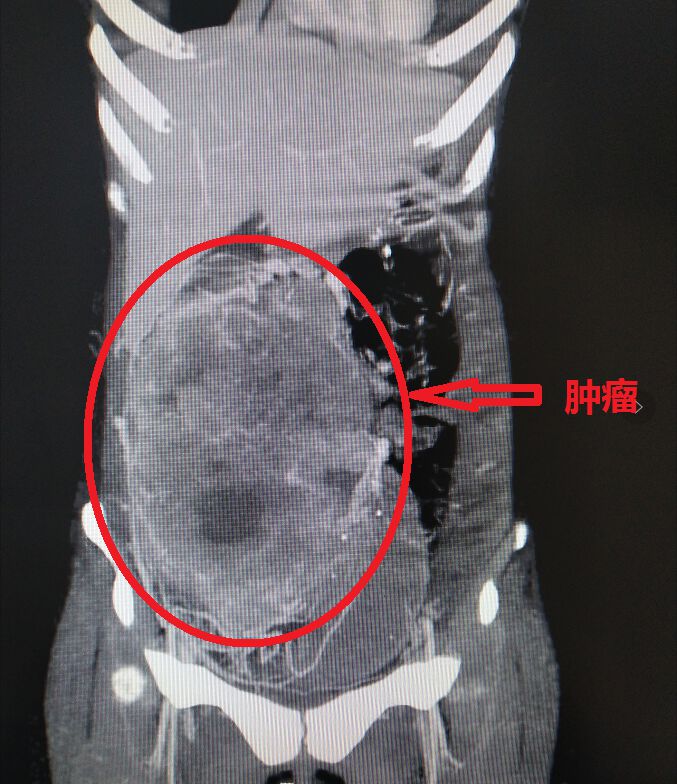

2020年3月中旬,小刘到中山大学附属第七医院消化医学中心就诊。CT检查发现:小刘体内的肿瘤体积非常大,从盲肠开始延伸到结肠肝区,占据了半个腹腔,肿瘤可能侵犯腹壁、后腹膜的器官,可见下腔静脉受压或被肿瘤侵犯而导致闭塞,无血流通过,肿瘤可能已经侵犯了大血管,手术风险很大。

▲CT检查见肿物占据半个腹腔存在侵犯大血管可能

但是,手术所面临的风险在于——下腔静脉是人体最大的静脉,一旦损伤,会造成严重的大出血。经放射科专家会诊,小刘CT检查的情况显示肿瘤导致了下腔静脉的血流中断,但是它在CT影像上的表现似有假包膜的改变,专家们认为,肿瘤压迫下腔静脉的可能性大,侵犯血管的可能性小。